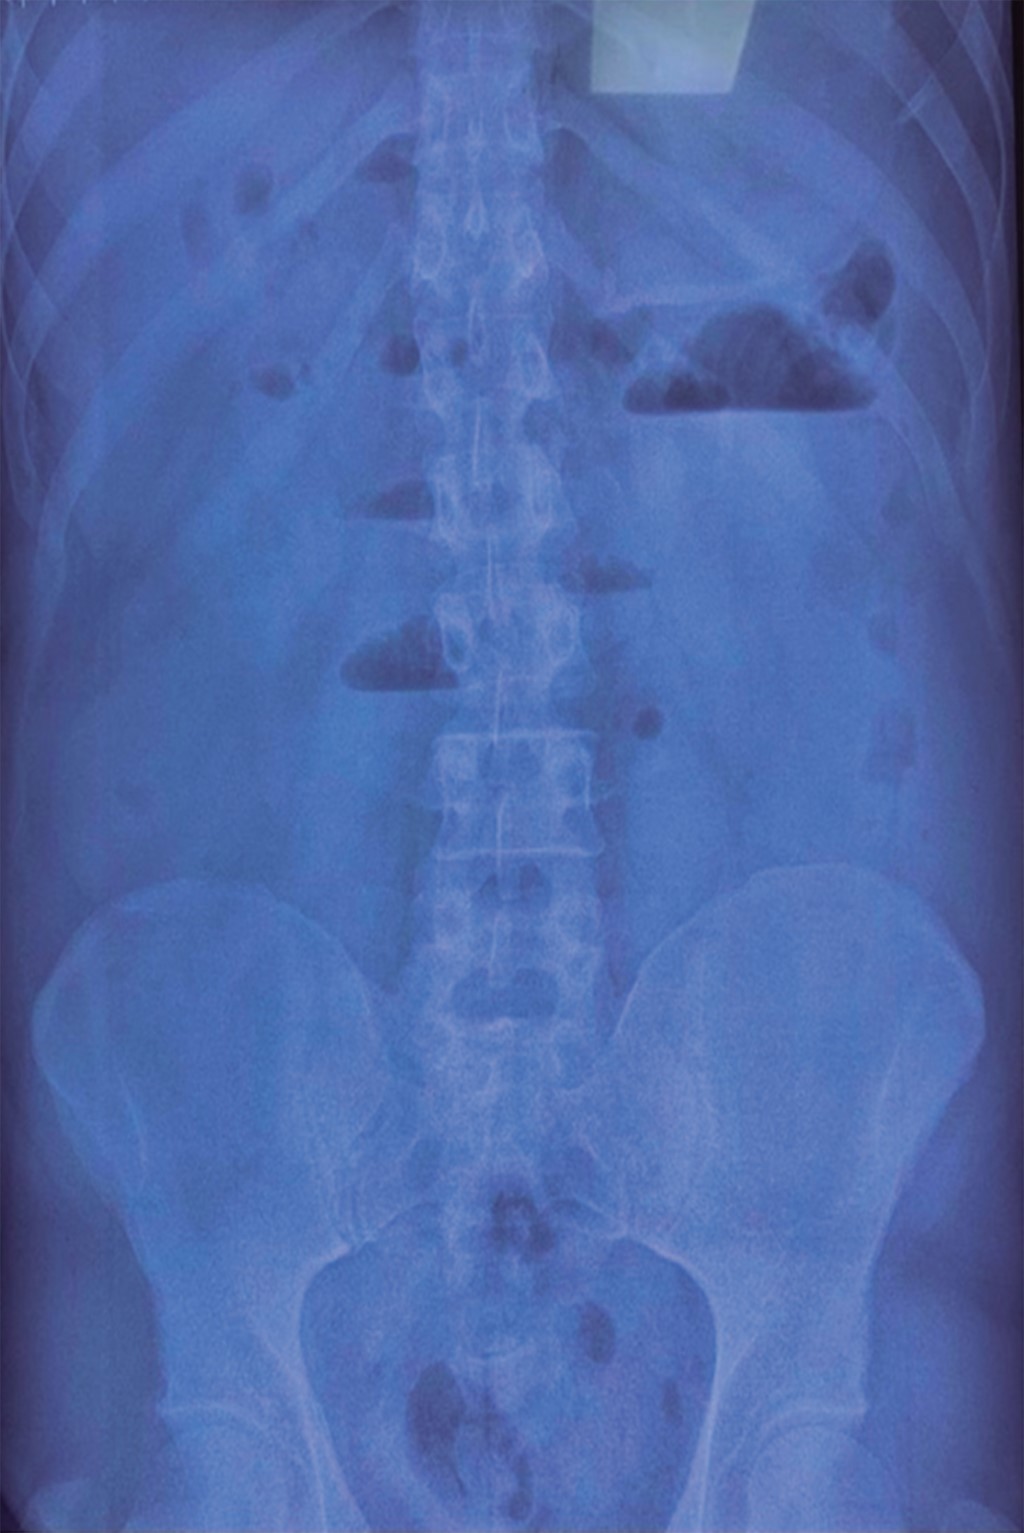

Tomografía simple y contrastada de abdomen (Figura 2): vía biliar intra y extrahepática normal, vesícula biliar no visible, colédoco y porta de calibre normales, páncreas y bazo de densidad, morfología y tamaño normal. Distensión de asas de yeyuno con retención de contenido líquido y mínimas burbujas aéreas dispersas en relación con su pared, aparentemente secundario a imagen redonda, de pared gruesa y contenido líquido de 31 mm de diámetro en íleon proximal. Apéndice cecal medial al ciego sin cambios inflamatorios con 44 mm de largo y 6 mm de espesor.

Por lo anteriormente descrito se realizó análisis de interrogatorio y cuadro clínico, cuya conclusión fue que se estaba ante un caso de oclusión intestinal alta de etiología a determinar, ya que el paciente no contaba con antecedentes quirúrgicos para considerar adherencias postoperatorias, las cuales son la principal etiología en estos casos, por lo que al tomar en cuenta el antecedente de litiasis vesicular en el paciente se reinterrogó de manera intencionada hasta encontrar una aparente relación con la ingesta de colecistocinéticos una semana previa a la intensificación de los síntomas, al mismo tiempo que se inició tratamiento médico para oclusión intestinal con analgesia, reposición hidroelectrolítica y colocación de sonda nasogástrica, con lo que se obtuvieron 400 ml de gasto fecaloide. Debido a falta de mejoría con dichas medidas, así como a los datos clínicos y paraclínicos de respuesta inflamatoria sistémica y a los hallazgos tomográficos: ausencia de visualización de la vesícula biliar, aire en fosa vesicular, pneumobilia (no reportado), distensión de asas de intestino delgado, probable cálculo biliar ectópico proximal a la válvula ileocecal y escaso líquido libre intraabdominal, se decidió someter a laparotomía exploradora bajo los siguientes diagnósticos prequirúrgicos: oclusión intestinal, íleo biliar vs perforación intestinal.

Los criterios diagnósticos de íleo biliar por tomografía son: signos de obstrucción de intestino delgado, cálculo ectópico, vesícula biliar anormal, colección de aire, presencia de niveles hidroaéreos o edema perivesicular con pared irregular.2 En nuestro caso, estuvo presente la triada de Rigler al momento de realizar la tomografía de manera que coincidió con lo registrado en la literatura.2 El ultrasonido es capaz de evidenciar la triada de Rigler en algunas series;6 sin embargo, en nuestro caso reportó posible apendicitis aguda complicada y fue capaz de determinar colecistitis aguda.

Figura 2